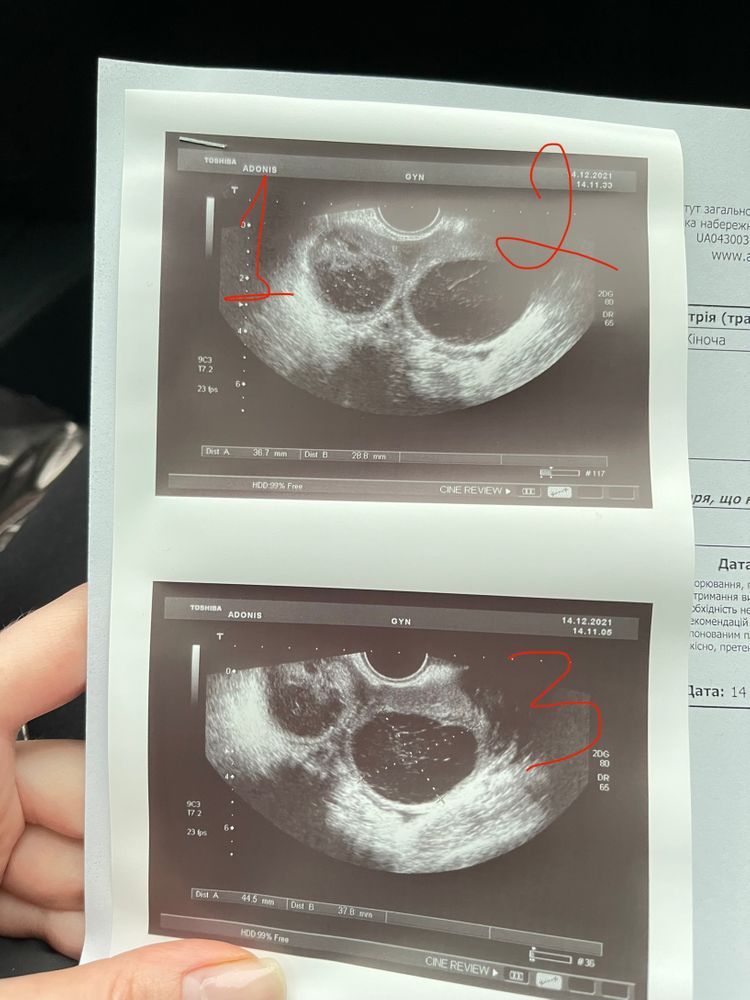

Тройная овуляция 🤭🤞🏻

Christina, спасибо !) первая 🙂 амг 3.8, у меня эндометриома в ПЯ)

Женя Ветлова, очень хорошее АМГ)) у меня год назад был 3.7 почти.. сегодня вновь пересдала. но мы собираемся на эко))) сдаем уже по-тихонечку анализы)) эхо у вас отличное, шикарное! дай бог, чтоб получилось все!

Женя, в поддержке был эстриол? Эндик нарос нешуточный, дай Бог не помешает имплантации. Ждём! По ощущениям тоже тройная была.

Виктория Север, нет, ничего нет в поддержке , сам вырос 🤪 13.3 написано в бумажке) на 6ДПО может там уже пошёл процесс имплантации ?😰 Ре эндометрий очень понравился, будем ждать чуда :) на стимуляции тоже?)

KUZOVOk, 😀 вообще перед уколом хгч было 2ДФ , и мы с Ре были немножко в шоке от третьего )))) спасибо большое 🥰